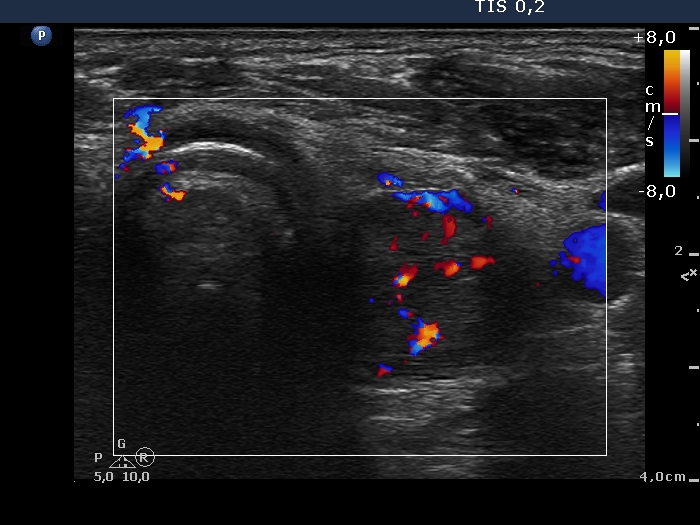

Left lobe, transverse scan, color Doppler mode. The vascularity is a bit increased.